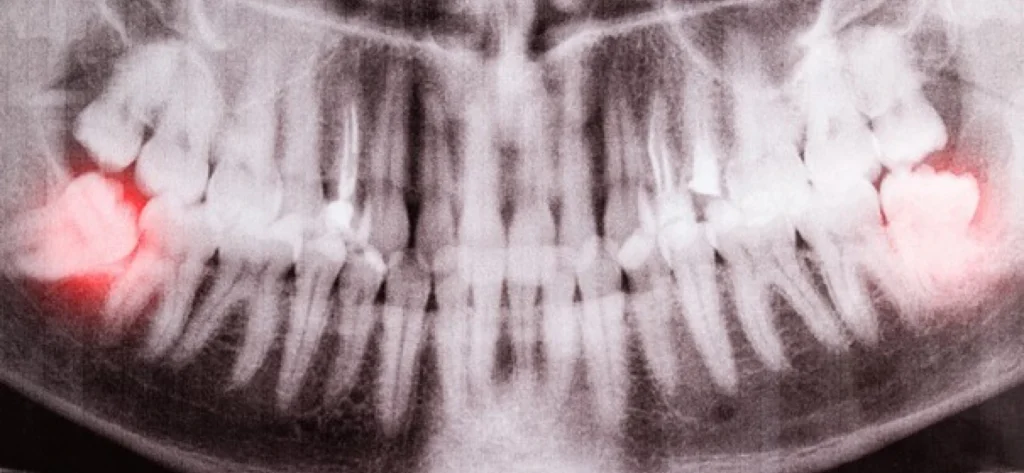

Au cabinet dentaire Claude Monet, nous utilisons des technologies radiographiques avancées pour évaluer avec précision les risques liés à vos dents de sagesse. Lorsque des problèmes tels que des dents impactées ou un risque de complications futures sont identifiés, nous discutons avec vous des différentes options de traitement. Notre objectif premier est toujours de maintenir votre confort et votre santé bucco-dentaire.